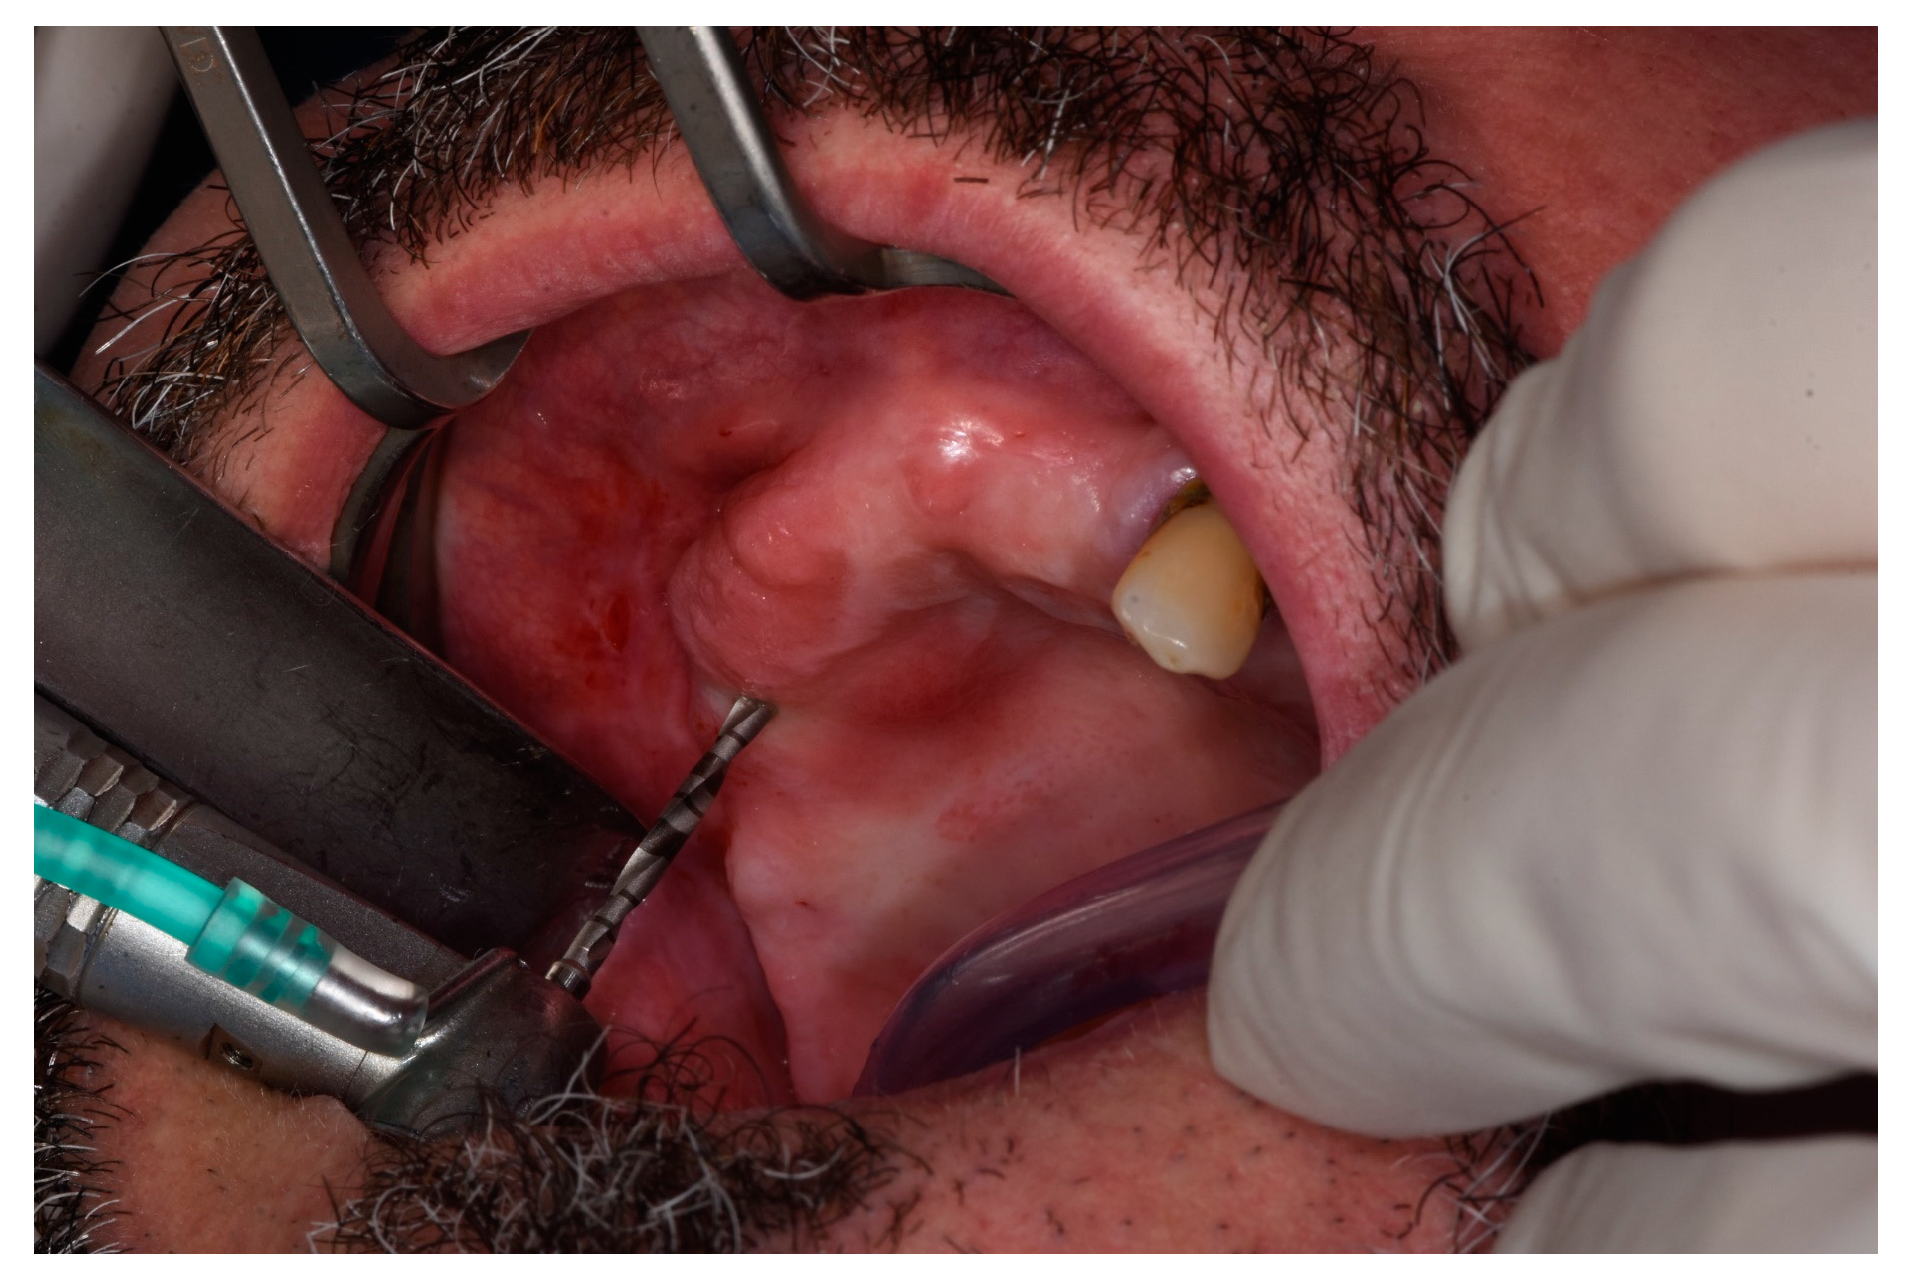

2. Materials and Methods

2.2. Surgical Procedures and Post-Operative Care